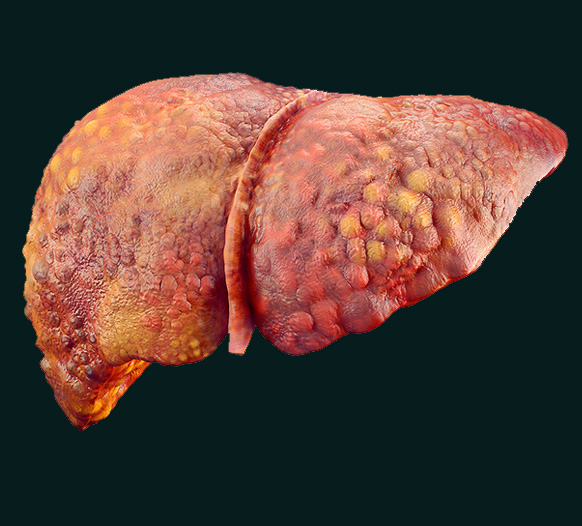

கல்லீரல் சிரோசிஸ் என்றால் என்ன?

ஆரோக்கியமான கல்லீரல் செல்களை அழற் (scar) திசைகள் மாற்றும்போது, கல்லீரல் சிரோசிஸ் போன்ற நோய்கள் ஏற்படுகின்றன. கல்லீரலின் ஜீரணம், புரத உற்பத்தி (இரத்த உறைப்புக் காரணிகள் உட்பட) மற்றும் மருந்து மற்றும் நச்சு வடிகட்டல் போன்ற முக்கிய செயல்பாடுகள் பாதிக்கப்படுகின்றன. ஆயுர்வேதத்தில் கல்லீரல் சிரோசிஸ் குணமடைதல், சில இயற்கை மூலாதாரங்கள் மற்றும் குணமடைதலின் தரத்தை மேம்படுத்தும் செயல்முறைகளின் மூலம் பெறப்படுகிறது.

கல்லீரல் சிரோசிஸ் ஏற்படுவதற்கான காரணங்கள் என்ன?

கல்லீரல் சிரோசிஸ் உருவாகுவதற்கு பல காரணங்கள் உள்ளன, அவற்றை கர்மா ஆயுர்வேத கல்லீரல் சிரோசிஸ் சிகிச்சை கீழ் ஆய்வு செய்கிறது.

- ஹெபட்டைட்டிஸ் C வைரஸ் தொற்று மற்றும் நீண்டகாலம், அதிக அளவு மதுவை உபயோகிப்பது, கல்லீரல் சிரோசிஸின் மிகவும் பரவலாக அறியப்பட்ட காரணங்களில் இரண்டாகும்.

- கொழுப்பு கல்லீரல் கொண்ட சில நபர்கள் சிரோசிஸை பெறலாம். உலகளாவிய அளவில், ஹெபட்டைட்டிஸ் B வைரஸ் தொற்று, சிரோசிஸின் முக்கிய காரணமாகும்.

- சில மரபணு தொடர்புடைய நோய்கள், கல்லீரலை பாதித்து, அதன் விளைவாக அழற் திசைகள் உருவாக, இறுதியில் சிரோசிஸாக மாறும்.

- கல்லீரலின் முதன்மை பண்பானது இரத்தத்தில் உள்ள நச்சுகளை நீக்குவது என்பதால், நச்சு தொடர்பான வெளிப்பாடுகள், கல்லீரலை பாதிக்கக்கூடும். அர்செனிக் போன்ற சுற்றுச்சூழல் மாசுபாட்டினால் நீண்டகால வெளிப்பாடு, கல்லீரல் சிரோசிஸை உருவாக்கக்கூடும்.

கல்லீரல் சிரோசிஸ் ஆயுர்வேத சிகிச்சை கல்லீரல் நிலையை உயிர்ப்பூண்டுவதையும், அதன் செயல்பாட்டையும் மேம்படுத்துவதையும் நோக்குகிறது. சிரோசிஸ் என்ற நோய், அதிகமான அழற் திசைகள் உருவாகுவதால் காலப்போக்கில் மோசமாகி விடுகிறது. ஆரம்பத்தில், உங்கள் உடல் குறைந்த கல்லீரல் செயல்பாட்டை சமநிலைப்படுத்த முயற்சிக்கும் போது, அதனை நீங்கள் அதிகமாக கவனிக்கக்கூடாது.